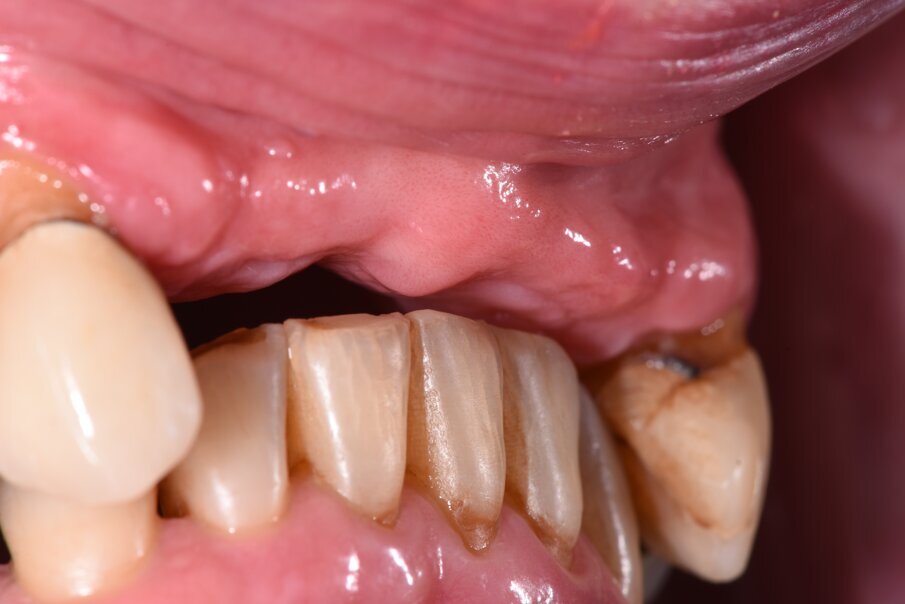

Nell’arcata inferiore dopo il trattamento parodontale abbiamo mantenuto inalterato il V° sestante provvedendo alla rimozione del 3.7 mesio-inclinato con sondaggio e mobilità difficilmente recuperabili e sostituendolo con un impianto. La scelta implantare poco convenzionale ha previsto per la sostituzione bilaterale dei diatorici con impianti in titanio di differente forma e connessione, inserendo bone level (BL) sui premolari e tissue level (TL) sui molari con una protesizzazione mista. La scelta del BL o del TL era rivolta a un aspetto estetico sui premolari e di maggior rispetto tessutale sui molari. Durante le fasi di prova (Fig. 41) si valutano le compressioni dei tragitti transmucosi (Fig. 42), gli eventuali precontatti, si finalizzano le forme e si rileva nuovamente il colore secondo la tecnica di depolarizzazione (Fig. 43).

Fig. 41_Al momento della prova ci sono aspetti tecnici e biologici da valutare, infatti è importante capire se il tessuto si ischemizza, segno di una sofferenza. Data dalla compressione che è da evitare inoltre se sono state create ovettature gengivali capire se sono rispettati gli spazi per il passaggio di scovolini e ausili per il mantenimento e la detersione.